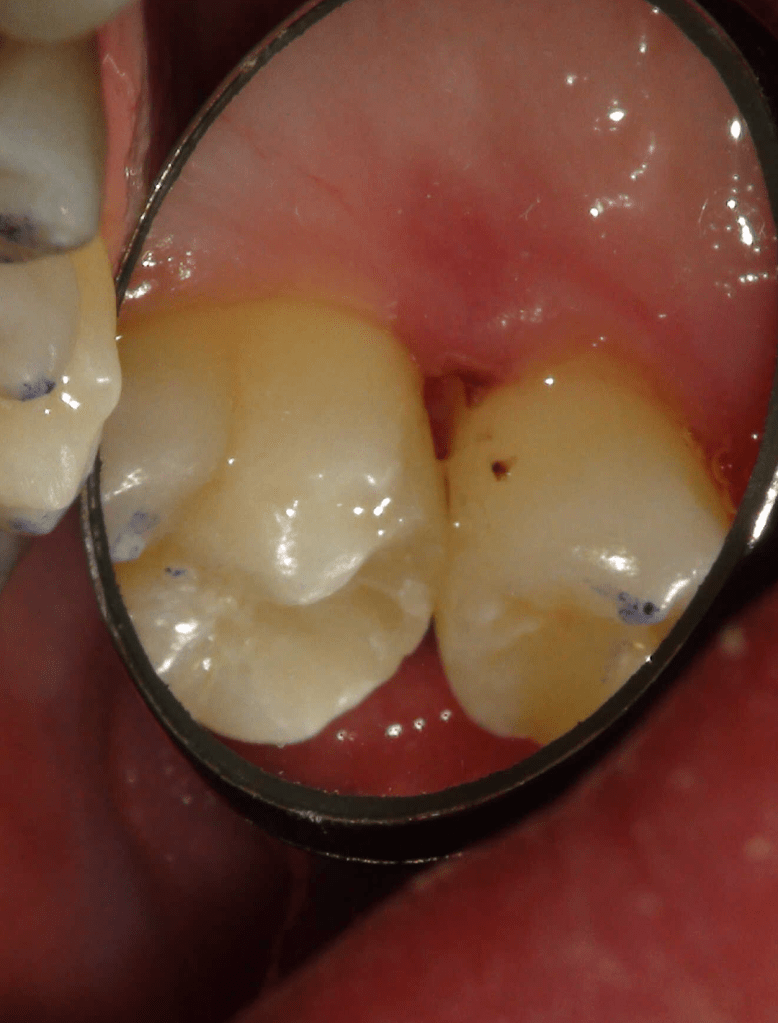

Diagnóstico de fisuras y fracturas

Fisura, remoción amalgama para explorar